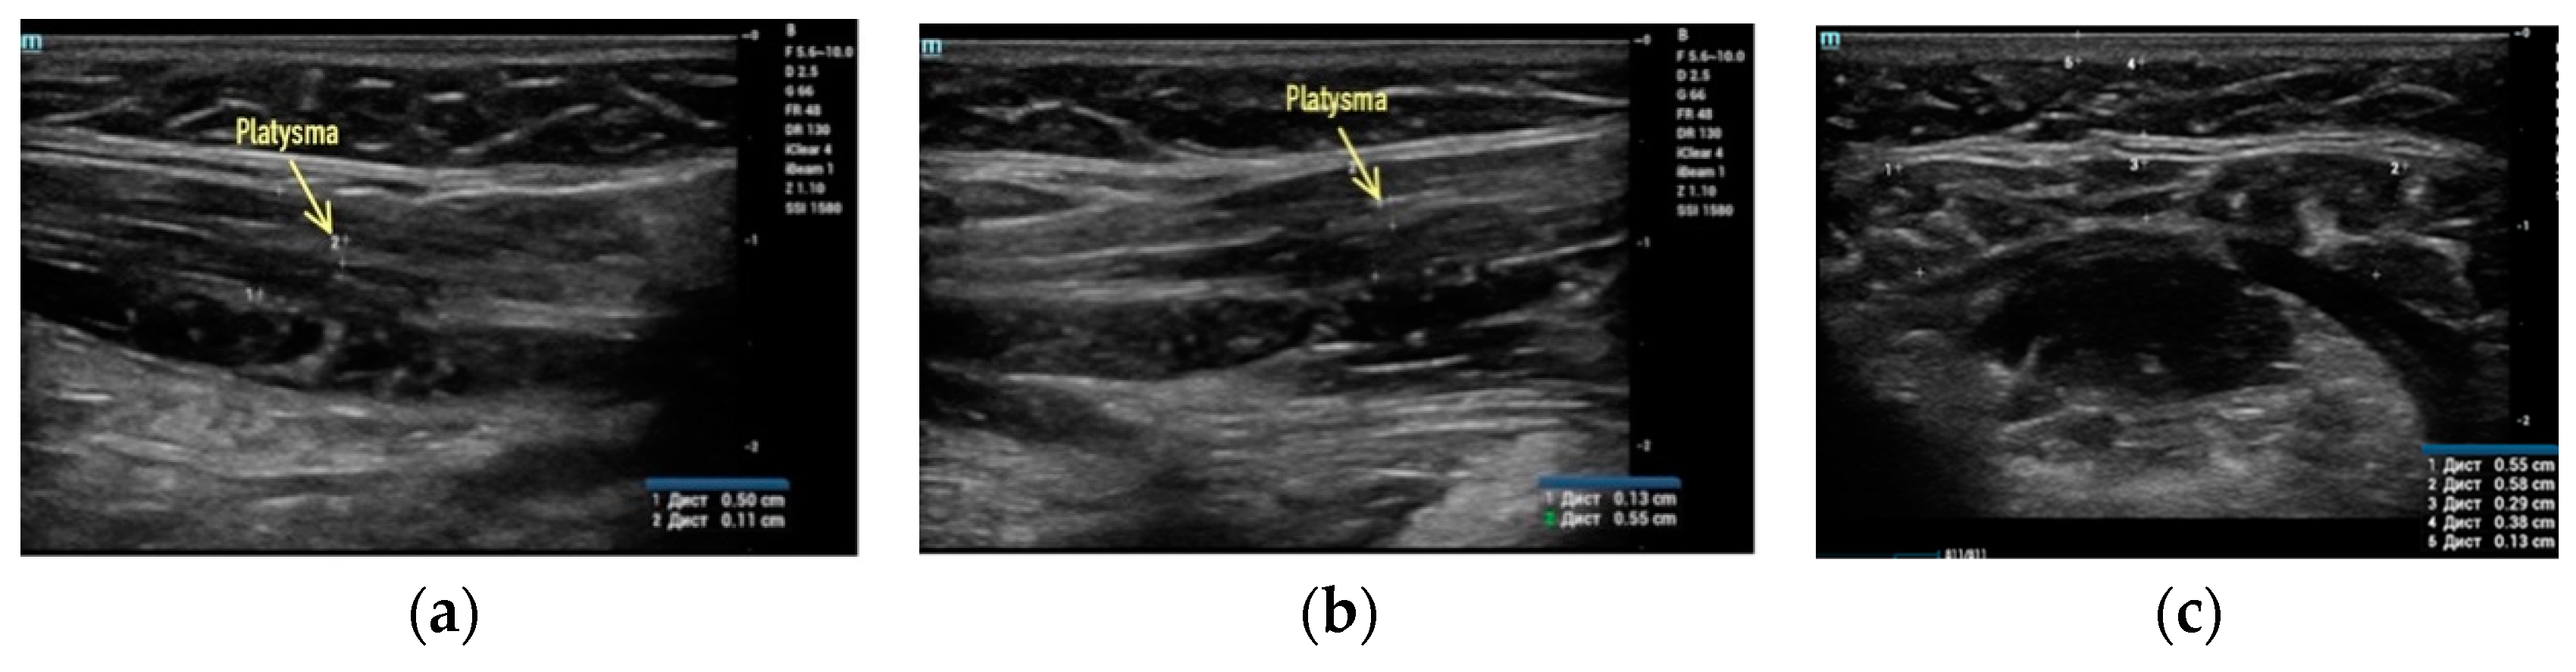

- Sharobaro, V.; Alimova, S.; Telnova, A.; Shamanaeva, L. Ultrasound diagnosis of age-related involutional changes in the lower third of face and neck to determine treatment techniques. Pak. J. Med. Sci. 2021, 37, 272–276. [Google Scholar] [CrossRef]

- Alimova, S.M.; Sharobaro, V.I.; Telnova, A.V.; Stepanyan, E.E. Planning of methods of surgical correction of soft tissues of the face and neck. Med. Vis. 2021, 25, 47–52. [Google Scholar] [CrossRef]